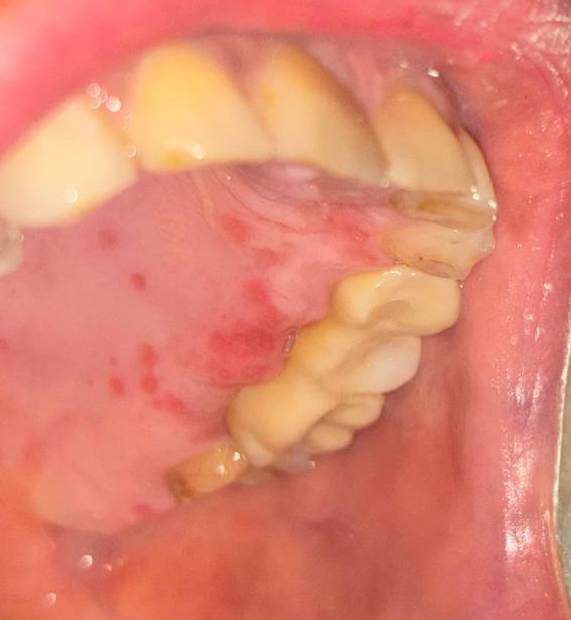

руслана Опубликовано 1 сентября, 2025 Поделиться Опубликовано 1 сентября, 2025 Здравствуйте. Поставили мост на двух имплантах. Было очень больно.даже с небольшой анестезией. Делали надрез слизистой и после этого затянули мост. Фиксация винтовая. Сразу сделали снимок . Все хорошо.Болей после установки не было. Но десна сильно отекла. Прошла неделя . десна до сих пор отечна. И какие то красные пятна. Скажите это нормально? Почему боль при установке коронок. До этого был опыт так больно не было. Врач говорит что это хорошо. Много десны. Нужно ли идти срочно к врачу с отеком или все заживёт. Накусывать не больно. Но десна все еще раздражена. Ссылка на комментарий

сирена Опубликовано 3 сентября, 2025 Поделиться Опубликовано 3 сентября, 2025 Заживёт. По фото похоже на рецидив герпеса, бывает после анестезии, процесс уже в стадии разрешения, скоро выздоровеете. А вот если красные пятна уйдут, а отёк останется, надо показаться доктору. Ссылка на комментарий